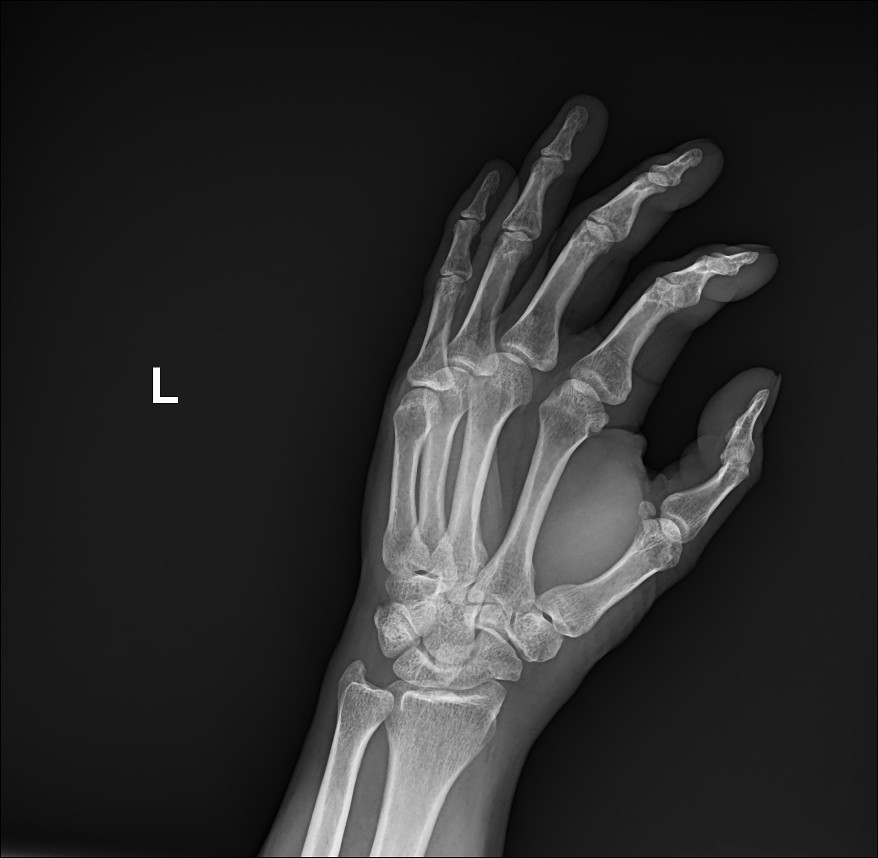

Oblique